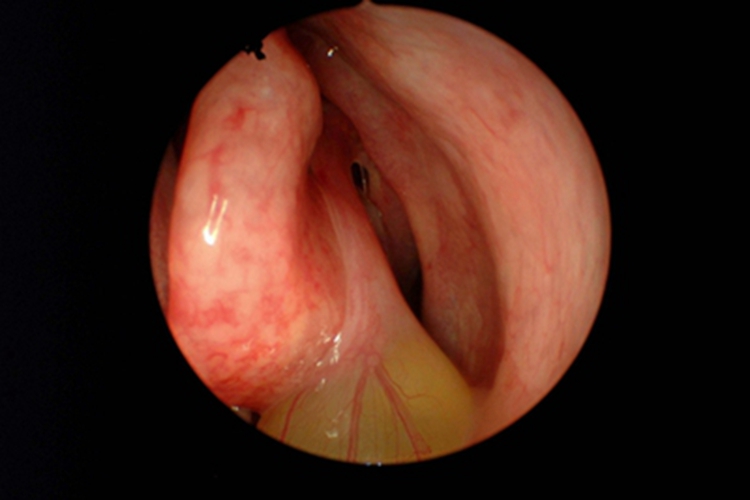

急性化脓性鼻窦炎可出现鼻腔黏膜肿胀,内有大量脓性或黏脓性鼻涕,鼻涕为黄色或黄绿色黏稠样,偶可带有少许血液,难以擤尽,也不易从鼻腔流出,可向后流至咽部,伴有咽痒、恶心等症状。